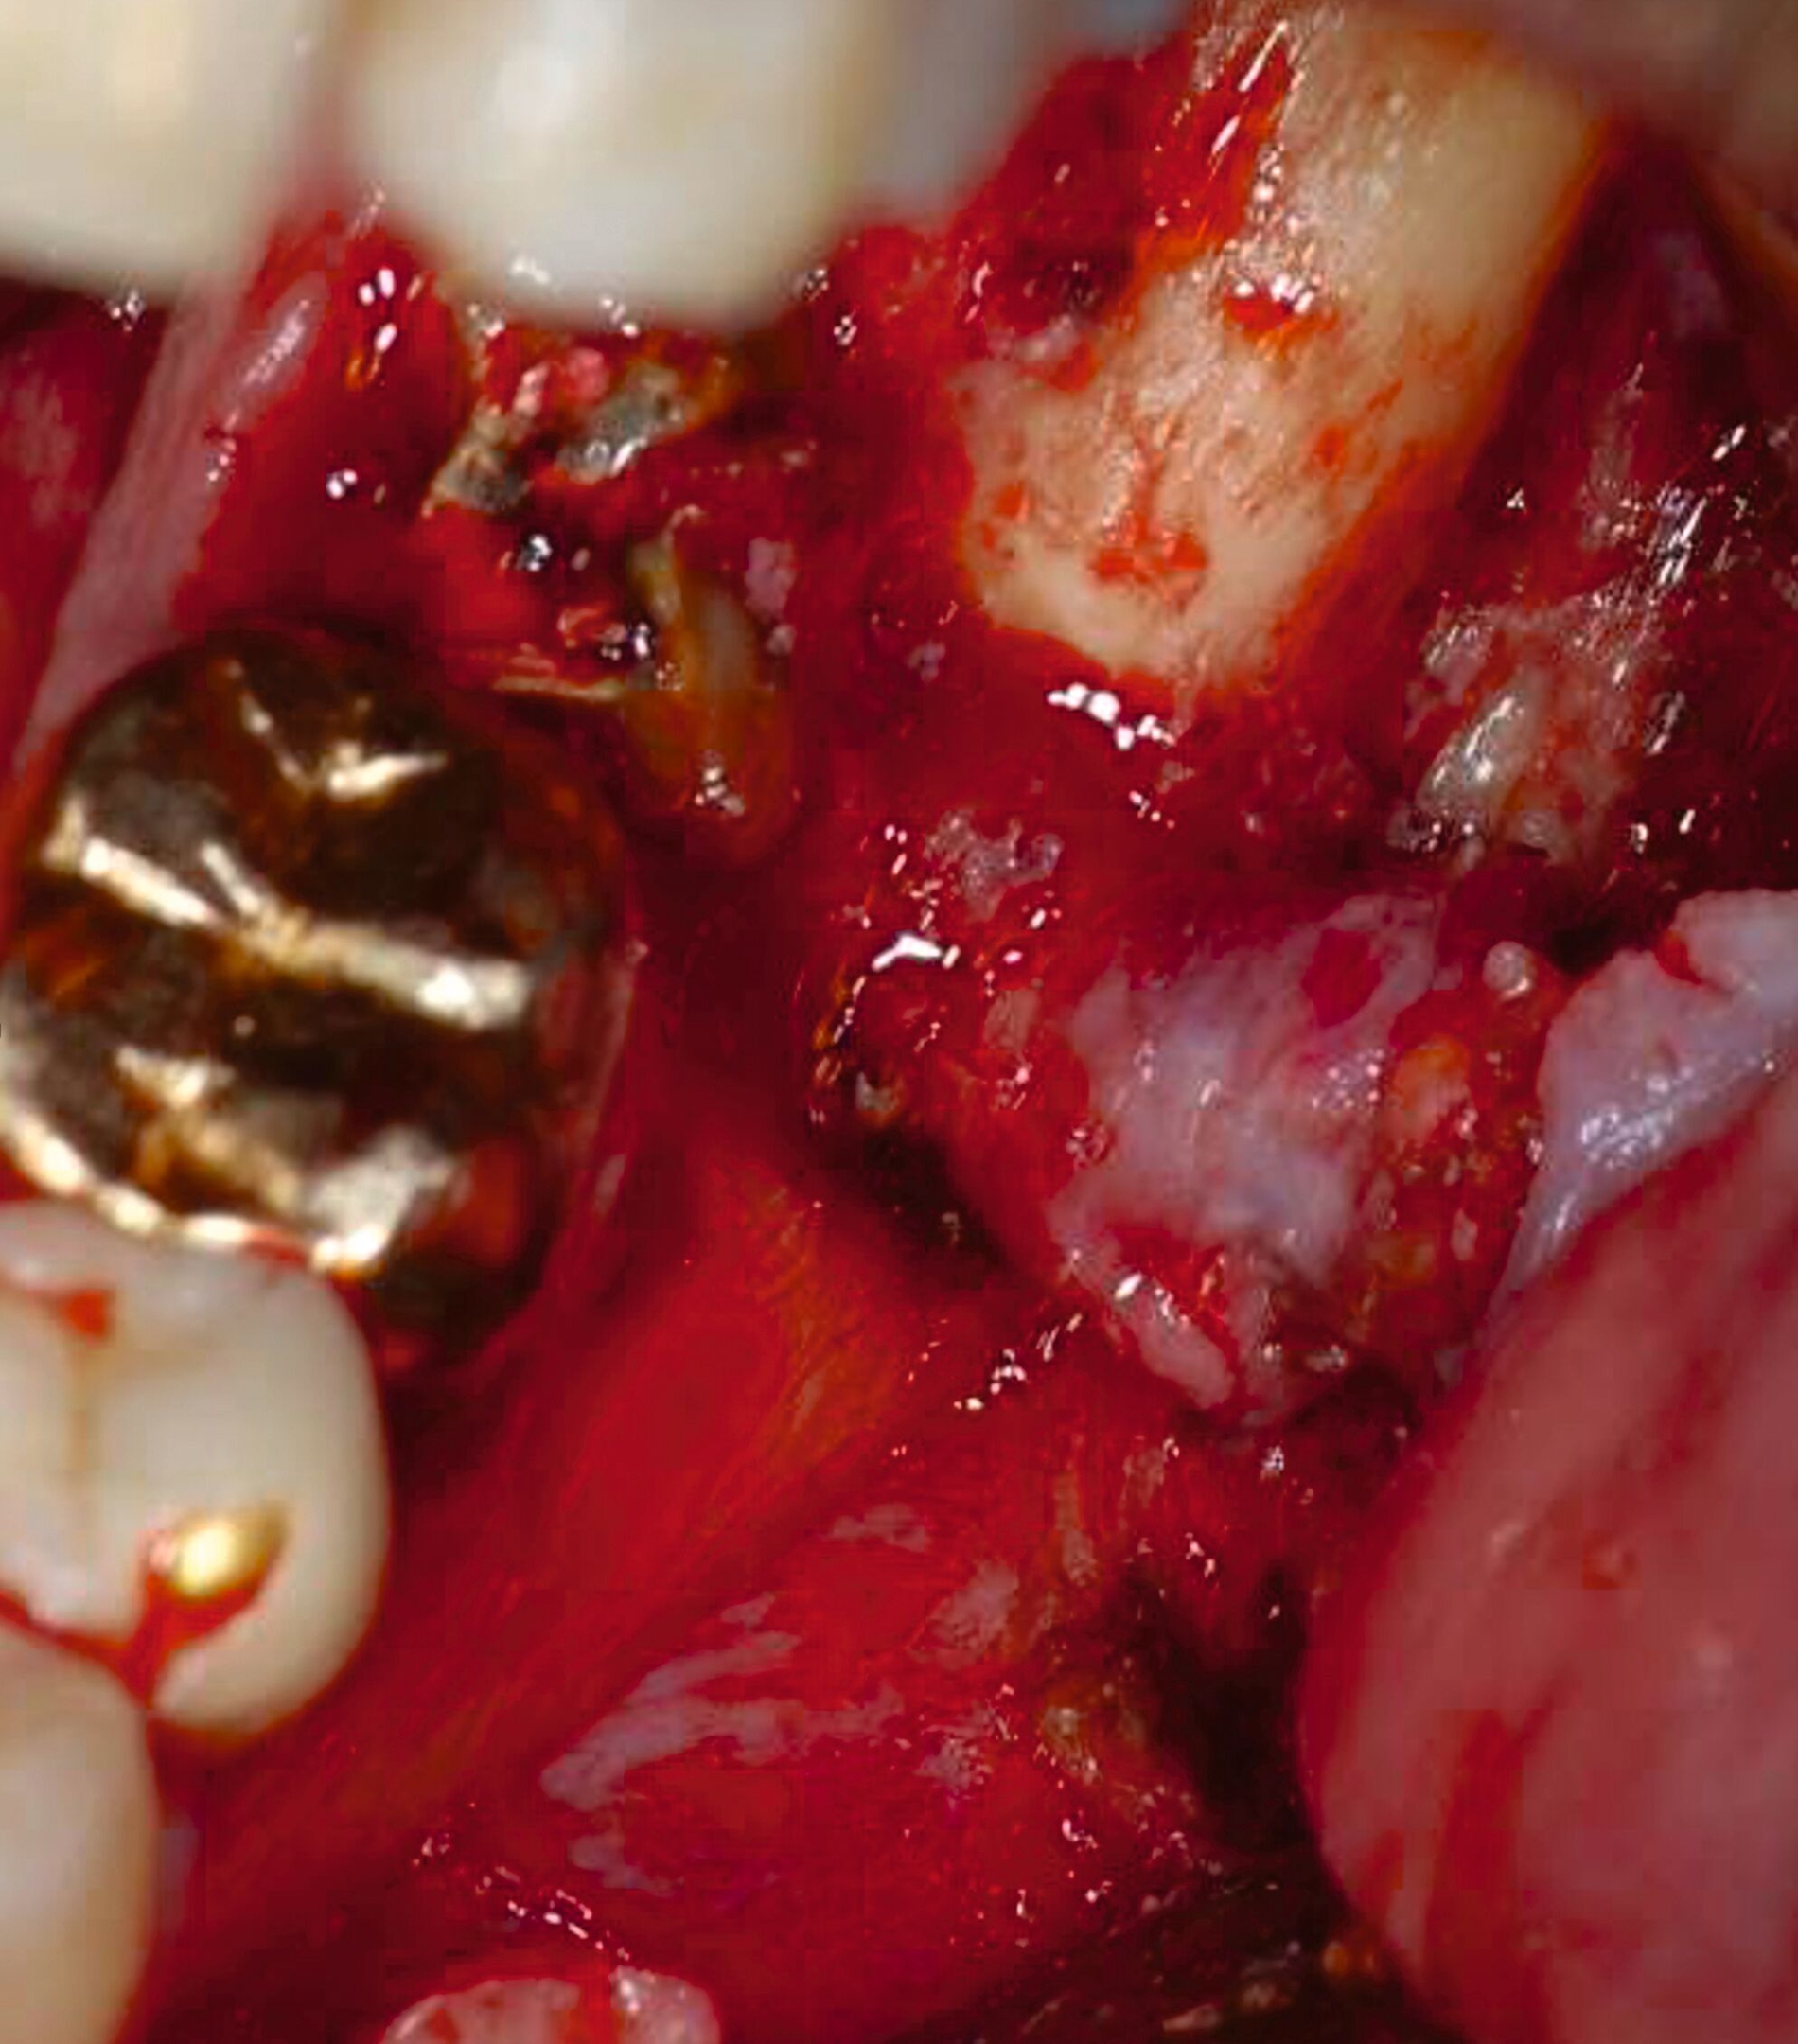

Nach der Planung des Eingriffs wurde der Patient in Intubationsnarkose operiert. Unter vorsichtiger Präparation und Darstellung des Alveolarknochens in Regio 37 ließ sich der bereits sonografisch beschriebene Fistelgang darstellen (Abbildung 5). Anschließend wurde Zahn 37 extrahiert und der entstandene Fistelgang chirurgisch revidiert (Abbildung 6). Die histopathologische Aufbereitung ergab dicht lymphoplasmazellulär infiltriertes Bindegewebe mit zystischer Aufweitung und einer epithelialen Auskleidung. Nach Abschluss der Wundheilung zeigte sich ein zufriedenstellendes kosmetisches Ergebnis ohne Anzeichen eines Rezidivs. Die Wurzelfüllung an Zahn 36 wurde in der Folge revidiert und in der Kontrollaufnahme nach einem Jahr waren keine Auffälligkeiten mehr zu erkennen.